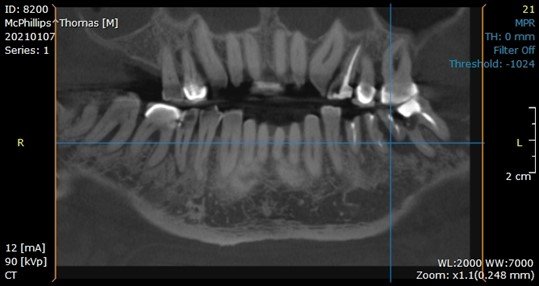

After a thorough dental and medical evaluation, including a complete set of x-rays and CBCT, a plan was developed for him. This included the removal of all broken and infected teeth, rebuilding the lower anterior teeth to improve his anterior occlusion, restoring the teeth that could be saved, and placing implants in the future edentulous sites of the lower arch. You can see on the x-rays and CBCT these areas.